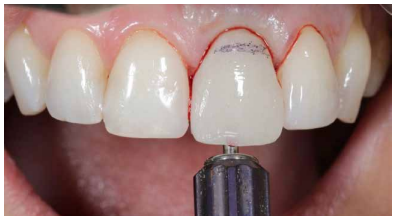

Caso clínico: Se presenta el caso de una paciente mujer de 32 años de edad, que acude por presentar una posible fractura radicular del incisivo central superior izquierdo (ICSI), acompañada de la aparición de un absceso periodontal en la región del fondo de vestíbulo de dicho diente. Tras llevar a cabo la exploración clínica y radiológica, se establece que el pronóstico del ICSI es desfavorable para llevar a cabo un tratamiento conservador del mismo. Tras la valoración de las características clínicas del caso presente, el plan de tratamiento se inclinó por la realización de la exodoncia del ICSI con la colocación simultánea de un IOI postextracción y la carga inmediata con una prótesis provisional del mismo.

Clinical case: We present the case of a 32-year-old female patient who presented with a possible root fracture of the upper left central incisor (ULCI), accompanied by the appearance of a periodontal abscess in the region of the bottom of the vestibule of said tooth. After carrying out the clinical and radiological examination, it is established that the ULCI prognosis is unfavourable for carrying out conservative treatment of the tooth. After assessing the clinical characteristics of the present case, the chosen treatment plan was to extract the ULCI with the simultaneous placement of a post-extraction osseointegrated implant (OII) and immediate loading of a provisional prosthesis on the implant.

Los beneficios de la carga inmediata incluyen una reducción notable de las intervenciones quirúrgicas, una menor dilatación temporal del tratamiento e incluso un mejor bienestar psicológico y social para el paciente. En casos con importante compromiso estético, la carga inmediata o la provisionalización inmediata, añadida a la colocación inmediata postextracción del IOI permiten minimizar las alteraciones derivadas de la pérdida dental, manteniendo el perfil de emergencia, contorno de tejidos blandos y las papilas gingivales5-7.

Conclusiones: La rehabilitación sobre implantes en situaciones de pérdida dental en el sector anterior estético y en especial, en pacientes jóvenes, requiere un plan de tratamiento multidisciplinar en cuanto a la extracción del diente y colocación del IOI en la posición tridimensional correcta, existiendo diferentes aspectos a tener en cuenta para ello, especialmente el remanente óseo residual, la posición del margen gingival, así como la preservación y acondicionamiento de los tejidos duros y blandos periimplantarios mediante injertos y un manejo correcto de una prótesis provisional hasta conseguir un perfil de emergencia y contorno gingival ideal antes de la corona definitiva

Conclusions: Rehabilitation on implants in situations of tooth loss in the aesthetic anterior sector, especially in young patients, requires a multidisciplinary treatment plan in relation to tooth extraction and placement of the OII in the correct three-dimensional position. There are various aspects to be taken into account, particularly the residual remaining bone, the position of the gingival margin, as well as the preservation and conditioning of the peri-implant hard and soft tissues by means of grafts and proper handling of a provisional prosthesis until an ideal emergence profile and gingival contour is achieved before the final crown.